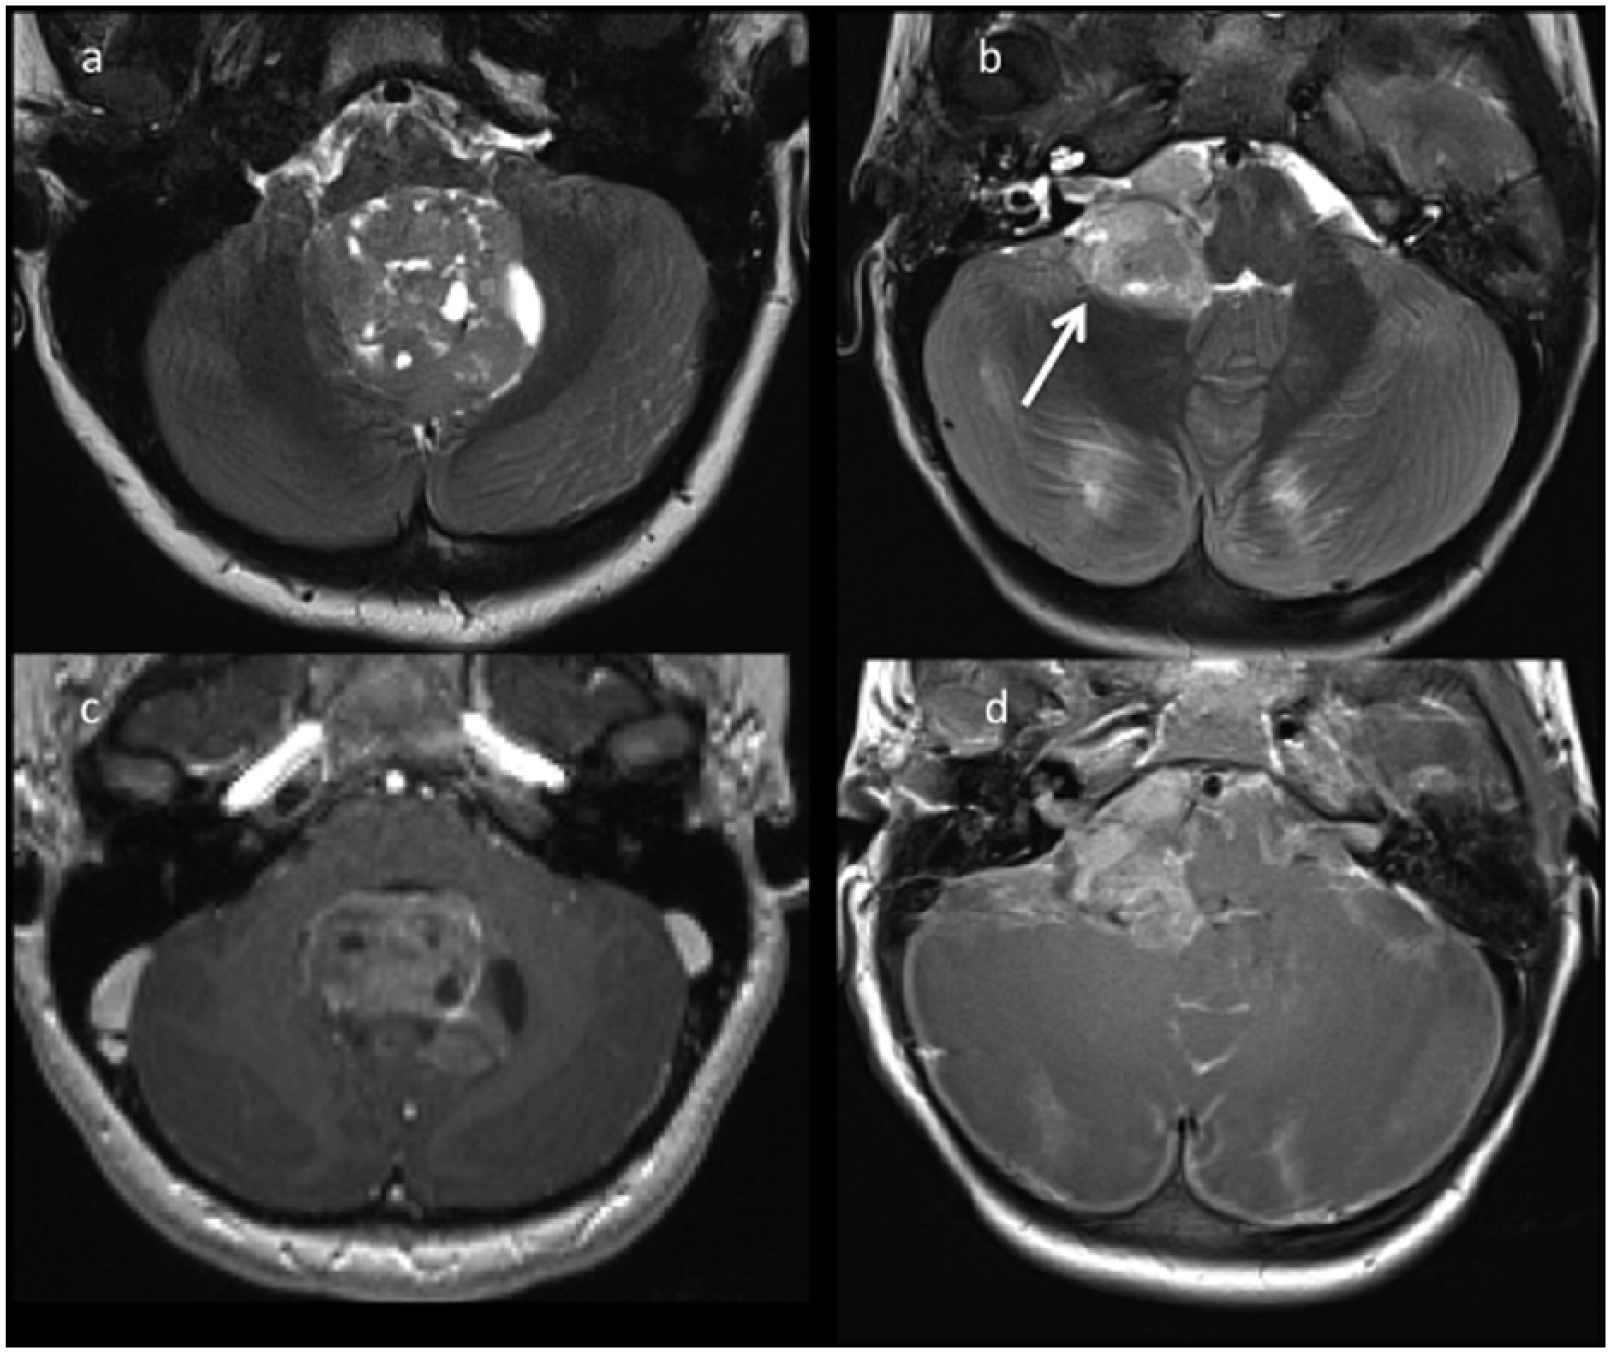

A single study on 143 children affected by medulloblastoma focused on 16 WNT tumors (11.8%) in order to highlight specific WNT MRI features, correlated with its embryologic origin. 60 Specifically, WNT tumors seem to develop along an oblique-curved triangle centered on the foramen of Luschka, with one peak extending ventrolaterally to the CP-angle cistern, another postero-infero-medially to the cisterna magna, and the third postero-supero-medially to the fourth ventricle (Figure 7). Previous studies observed that WNT tumors are located in the midline and always infiltrated the dorsal brain stem. The epicenter of the tumor had an important role in the evaluation, but tumor signal, cyst, necrosis and hemorrhage were also described through pre- and postoperative images. All WNT tumors seemed mostly extra-parenchymal and attached to the surface of the brain stem and/or the cerebellum. The dentate nucleus, the superior and the middle cerebellar peduncle, the lateral brain stem, the infero-medial portion of the cerebellar hemisphere, and the floor of the fourth ventricle were some of the structures invaded. A laterality score was introduced to complete pre- and postoperative evaluation. The obtained results offered the hypothesis that WNT tumors are close to the midline but they are lateralized; the source areas are around the foramen of Luschka, superficial layers of the dorsolateral brain stem under the middle cerebellar peduncle and paramedian structures of the inferomedial cerebellar hemispheres. These results were in line with the new information on the origins and pathway involved.10,60,61 The laterality and the dominantly extra-parenchymal location of WNT tumors seemed to confirm that the lower rhombic lip could be the origin.

Magnetic resonance image of an eight-year-old girl (a,c) and of a three-year-old girl (b,d), both presenting with WNT medulloblastoma. Axial T2w (a,b) images of two patients show two masses localized respectively in the fourth ventricle (a) and in the right cerebellopontine angle (arrow) (b). Axial T1w postcontrast (c,d) images show heterogeneous enhancement of the two lesions.

The relationship between the medulloblastoma and the brain stem was also evaluated: fewer than half (48%) of SHH tumors showed contact with the brain stem or an intraventricular expansion (19%). All other subgroups always had this contact. The key points were cuneate nucleus for WNT, and cuneate and cochlear nucleus for Group 3 and Group 4; almost all (87.5% WNT, 100% Group 3 and Group 4) showed infiltration of the fourth ventricle. 27

SHH has most commonly involved the cerebellar hemispheres (54%) in the analysis of Perreault and colleagues, 20 and the preferential localization of SHH medulloblastomas in the cerebellar hemispheres (Figure 8), following the higher frequency of D/N medulloblastomas involvement in this site, seems to be justified by SHH tumor origins, 60 while cochlear nucleus onset of SHH medulloblastomas in younger patients is not supported by a different SHH tumor location between infants and older patients.10,62

MRI of a six-year-old girl (a,c) and of a two-year-old girl (b,d) presenting with a classic and a desmoplastic SHH medulloblastoma. Axial T2w (a,c) images of two patients show two masses arising from the cerebellar hemispheres. Axial T1w postcontrast (c,d) images show almost no contrast enhancement of one lesion (c) and contrast enhancement in the other lesion (d).

A recent study analyzed a cohort of 71 patients with medulloblastoma to describe a correlation between molecular subgroups and location, broadening our understanding about the origins of molecular medulloblastoma subgroups. 63 An important observation was that all subgroups included some tumors that were only extracerebellar (37.5% WNT, 9.5% SHH, 13.3% Group 3, 22.2% Group 4), but only SHH medulloblastomas presented tumors that were only intracerebellar (52.4%). Hemispheric cerebellar tumor portions belonged mainly to the SHH subgroup. 63